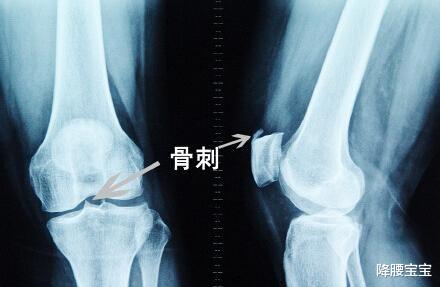

人上了年纪 , 经常会感到膝关节疼痛 , 尤其在半蹲位时疼痛更为明显 。 到医院一拍片 , 显示膝关节长“骨刺”了 , 举着片子问医生:“大夫您看 , 我的膝盖长骨刺了 , 您帮我想办法把骨刺拿掉吧!不然该更严重了……那么膝关节长骨刺怎么办?必须要除之而后快?

说起骨刺 , 很多人会望文生义 , 以为是骨头里长刺了 。 而事实上 , 骨刺 , 又称骨赘 , 专业叫法为骨质增生 。 之所以叫骨刺 , 并不是膝关节真的长了个刺 , 只是通过影像学检查的时候 , 看上去像刺 。

骨刺在中老年人群中非常普遍 , 是由于关节软骨经过长期运动产生磨损、破坏后 , 诱导了骨头修补、硬化与增生 , 产生骨头增生物 , 是一种自然的老化现象 。 就像脸上长皱纹一样 , 一般没什么影响 。

我们出现膝关节疼痛也不是因为骨刺“扎的” , 而是伴随骨刺产生的急性非感染性炎症 。 实质上就是膝关节骨性关节炎的一种表现 , 是骨关节边缘上由于长期慢性损伤引起瘢痕组织增生 , 天长日久可产生钙质沉着变成骨质而形成的 。 它是膝关节衰老到一定阶段的必然结果 。